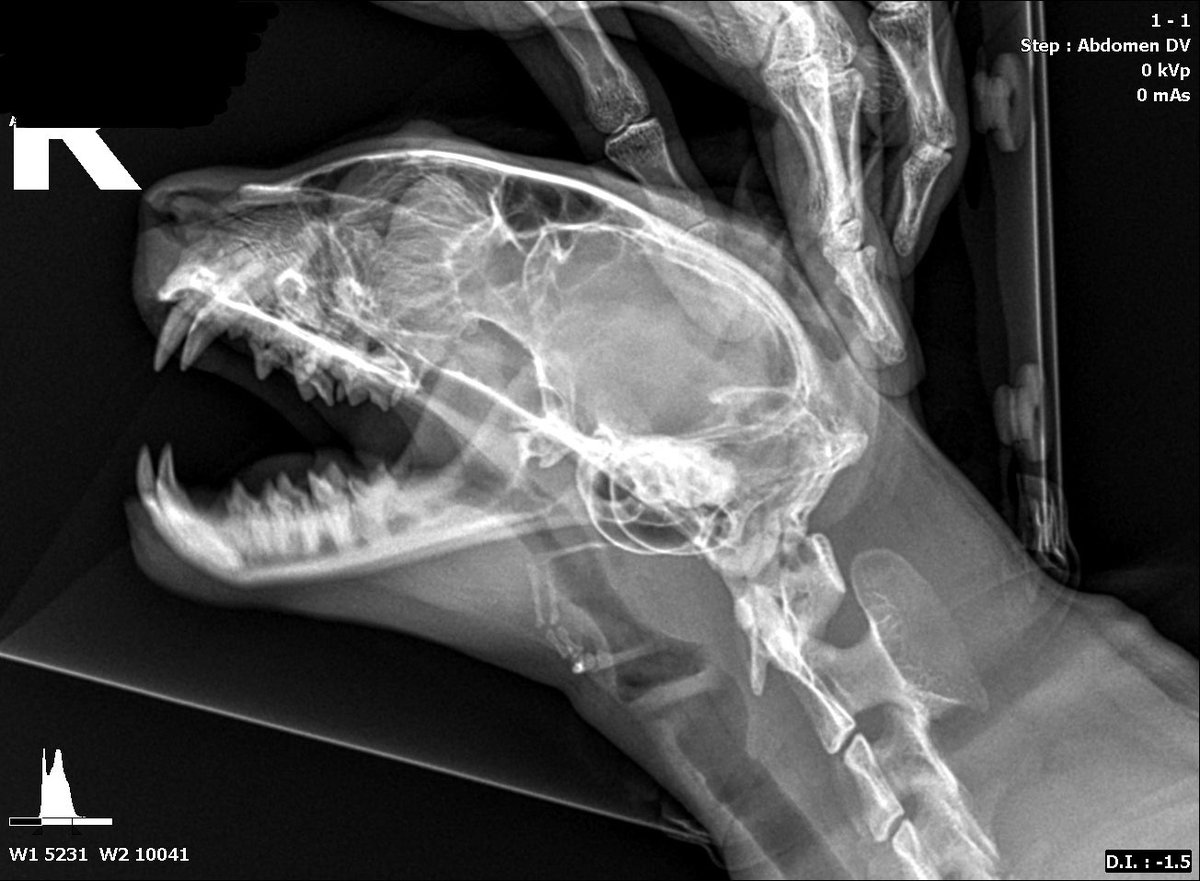

월간 공룡(아님)